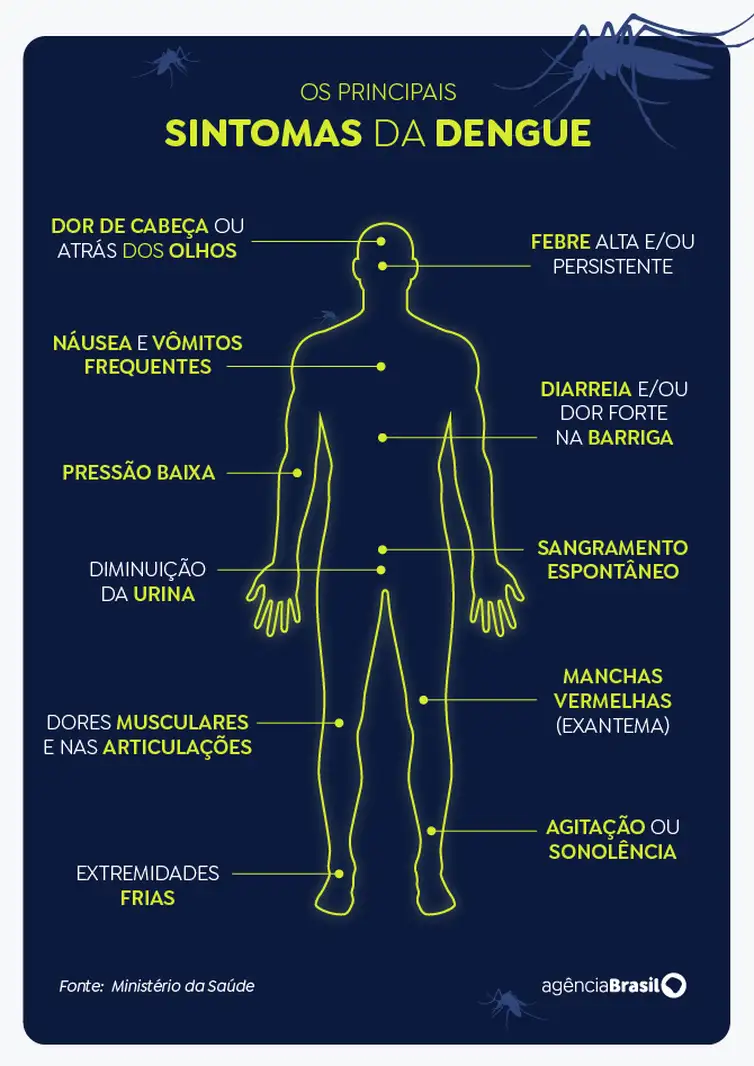

“Este aumento representa um quadro preocupante de saúde pública, considerando o risco elevado de complicações graves, tanto para elas quanto para os bebês. Formas graves da doença, como choque, hemorragias e óbito representam riscos para as gestantes, enquanto as complicações perinatais incluem prematuridade, restrição de crescimento intrauterino e morte fetal”, informou a pasta.